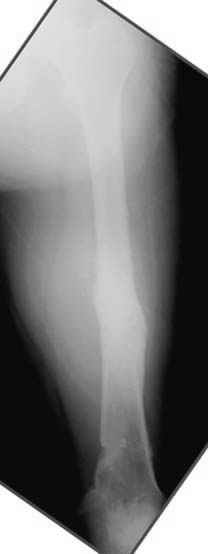

5:24 Рентгенограмма таза, вызывают врача ортопеда (снимок N1), его диагноз: закрытый переломо-вывих правого тазабедренного сустава, получает добро на закрытую репозицию в приемном отделении

N 2

На рисунке N1 предоперационный план лечения ложного сустава шейки бедра- линия ложного сустава, угол и направление введения импланта, клиновидная остеотомия в градусах и миллиметрах, второй снимок после коррекции, расчет, на сколько удлиняется конечность и размеры импланта;

N3 рисунок окончательный снимок, после операции моя рентгенограмма должен выглядеть примерно как эта картина. На N4 снимке клин перед удалением; N5 послеоперации 3 нед.; N6 окончательная рентгенограмма.

варус при проксимальном отделе 95 градусной пластиной.